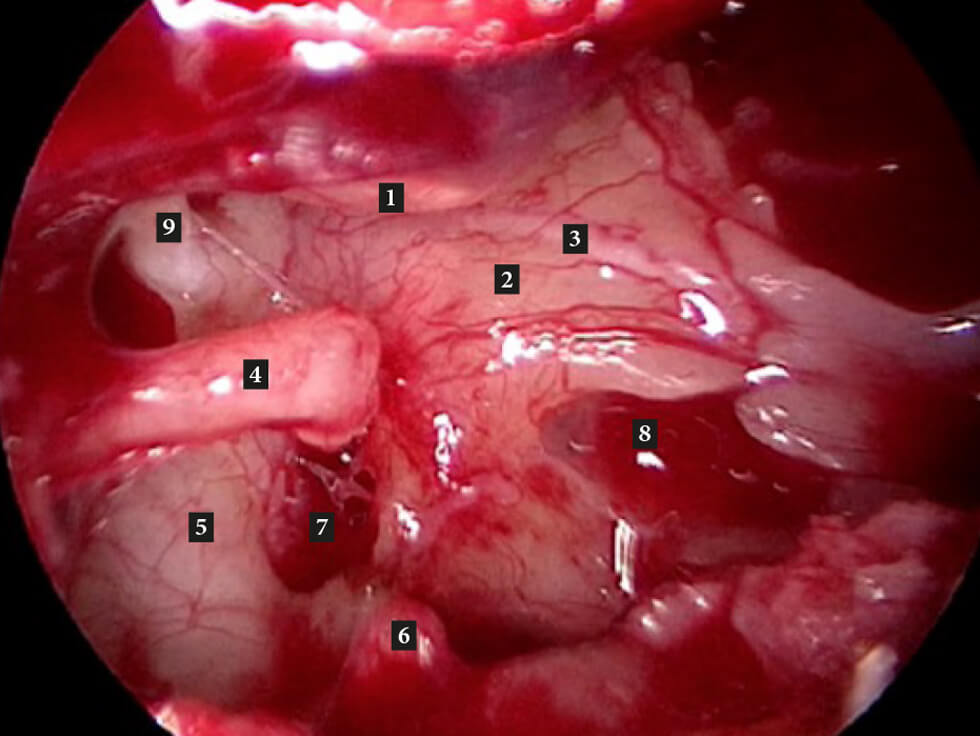

Figure B. Right middle ear (after removal of stapes suprastructure). 1. Handle of malleus; 2. Promontory;

3. Jacobsons nerve; 4. Long process of incus; 5. Tympanic segment of facial nerve; 6. Pyramid;

7. Oval window; 8. Round window niche; 9. Cochleariform process with tensor tympani tendon.